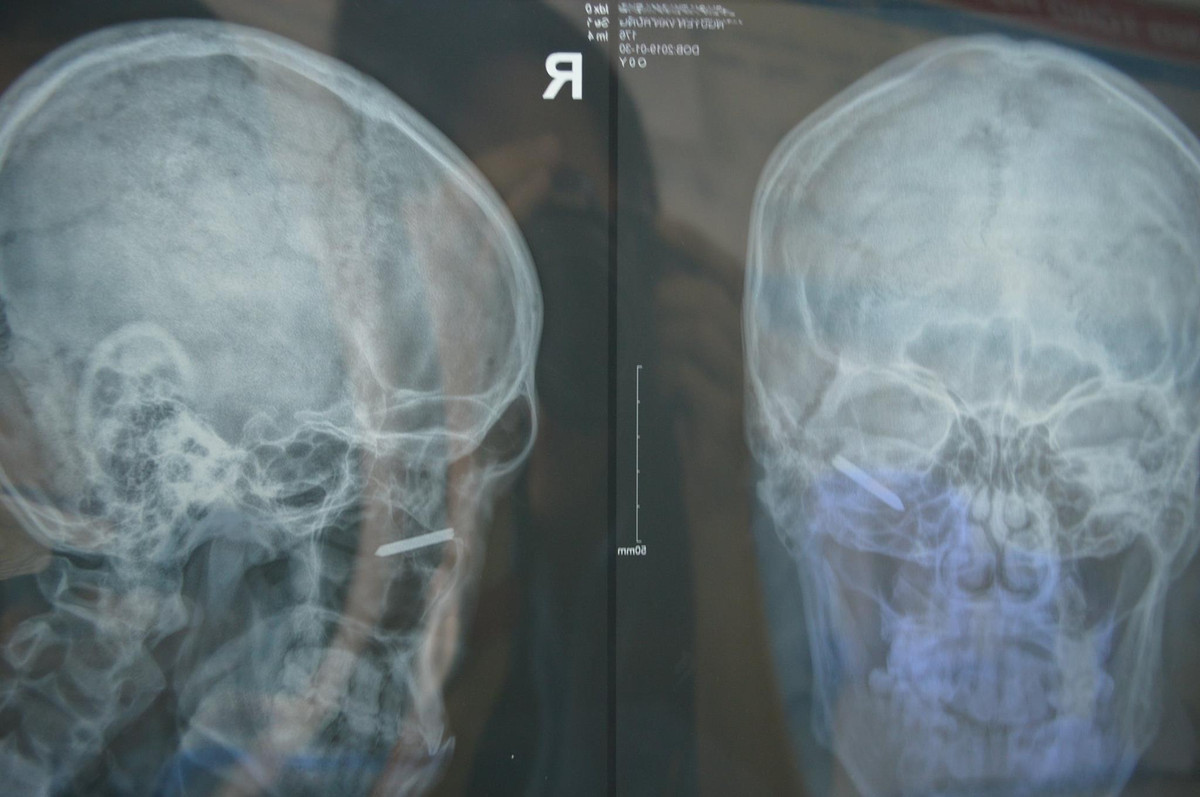

Sau khi nhập viện, bác sĩ cho biết anh bị dị vật là một cây đinh dài khoảng 3cm đang cắm sâu trong hốc mắt, rất gần nhãn cầu.

Cuộc phẫu thuật diễn ra căng thẳng sau hơn 30 phút do bác sĩ Cao Thành Quý - Phó khoa Mắt cùng sự phối hợp của bác sĩ thẩm mỹ Thái Thanh Duy và ê - kíp thực hiện. Do vết thương nhìn thấy chỉ là một vùng rách da nhỏ ở mi dưới ngoài nơi cây đinh xuyên qua, rất khó xác định đầu đinh vì đã cắm khá sâu (quan sát trên phim XQuang), có nguy cơ tụt vào xoang hàm khi có tác động.

| Hình ảnh vật nhọn nằm trong hốc mắt và khi được lấy ra |